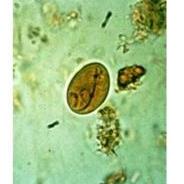

Odczynniki i materiały do analiz mikroskopowych